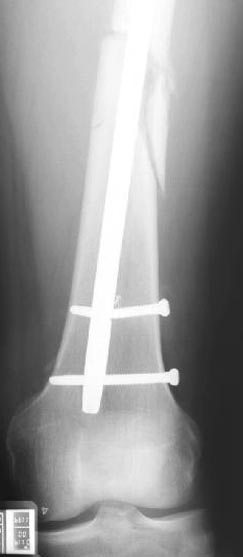

Снимки представлены: 1 мес; 3 мес; 1 год; 2 года, предоперационные и ротационная КТ грамма

Деформация:

Вальгус- 17 градусов

Рекурватум 5 градусов

Укорочение 2.5см

Ротационно 22 градусов внутренная

Смещение диафиза по поперечнику 75%

Операцию провели в два этапа, сперва удалили штифт, рассверливание римером на пару мм большего диаметра, определение чувствительности на анаэробную и аэробную культуру (где исследования показали негативный результат чувствительности), через дней десять - начали аппаратную фиксацию.